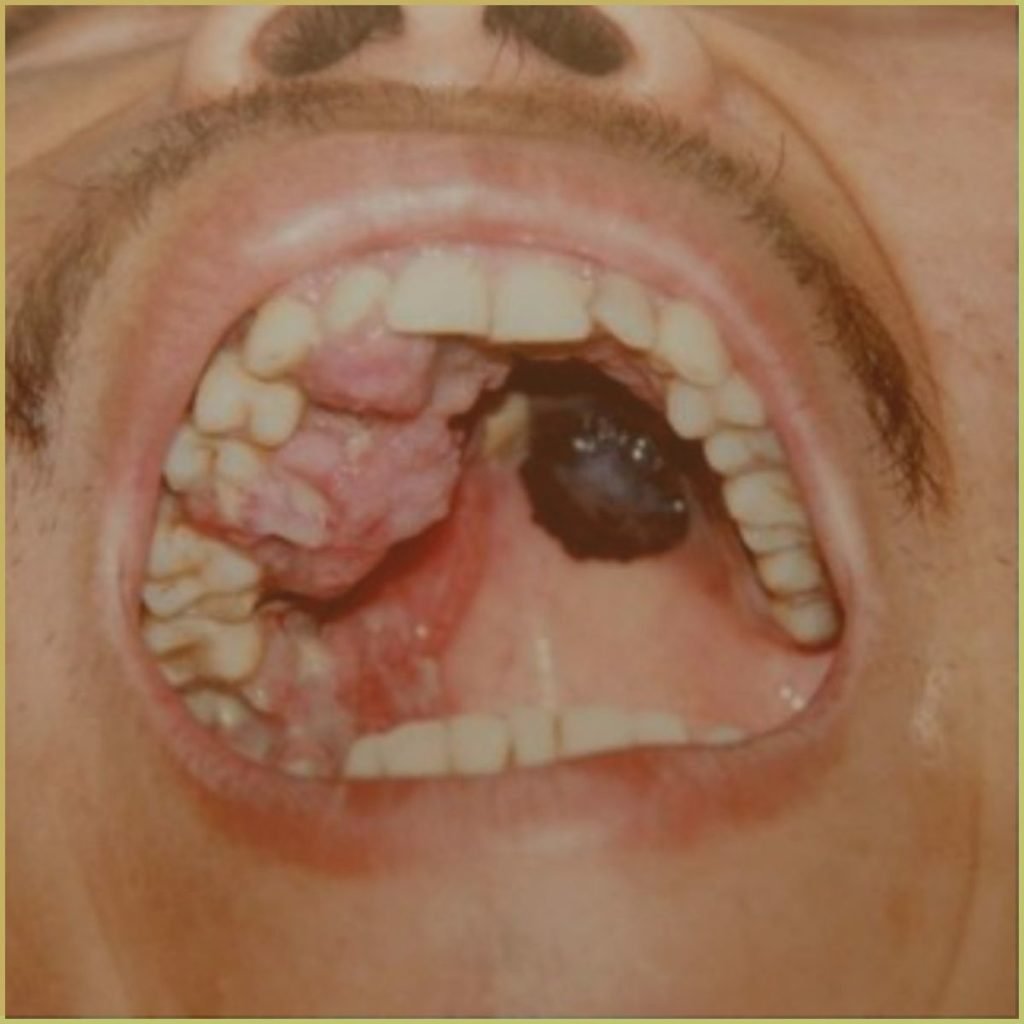

MELANOMA

Melanoma refers to a highly aggressive tumor that develops from cutaneous melanocytes derived from the neural crest cells in the basal layer of the epithelium. Oral malignant melanoma is an extremely rare malignancy. It has a higher tendency to metastasize to underlying tissues and a relatively low (<20%) 5 year survival rate. Risk factors for mucosal malignant melanoma include alcohol consumption, tobacco use, and denture irritation. The common clinical presentation includes:

- Early lesion – pigmented macular patch with irregular borders.

- Mature lesion – deeply pigmented nodular lesion with possible ulceration.

- Usually seen on the maxillary gingiva and hard palate.

Diagnosis is based on the lesion history, clinical presentation and microscopic findings, which may include:

- Atypical melanocytes (hyperchromatism and nuclear pleomorphism)

- Advanced lesions may include infiltration into lamina propria and muscle.

- Positive immunohistochemical markers (S-100, HMB-45, fatty acid synthase).

Treatment options include:

- Surgical excision (wide margin).

- Neck dissection in cases of deep invasion.